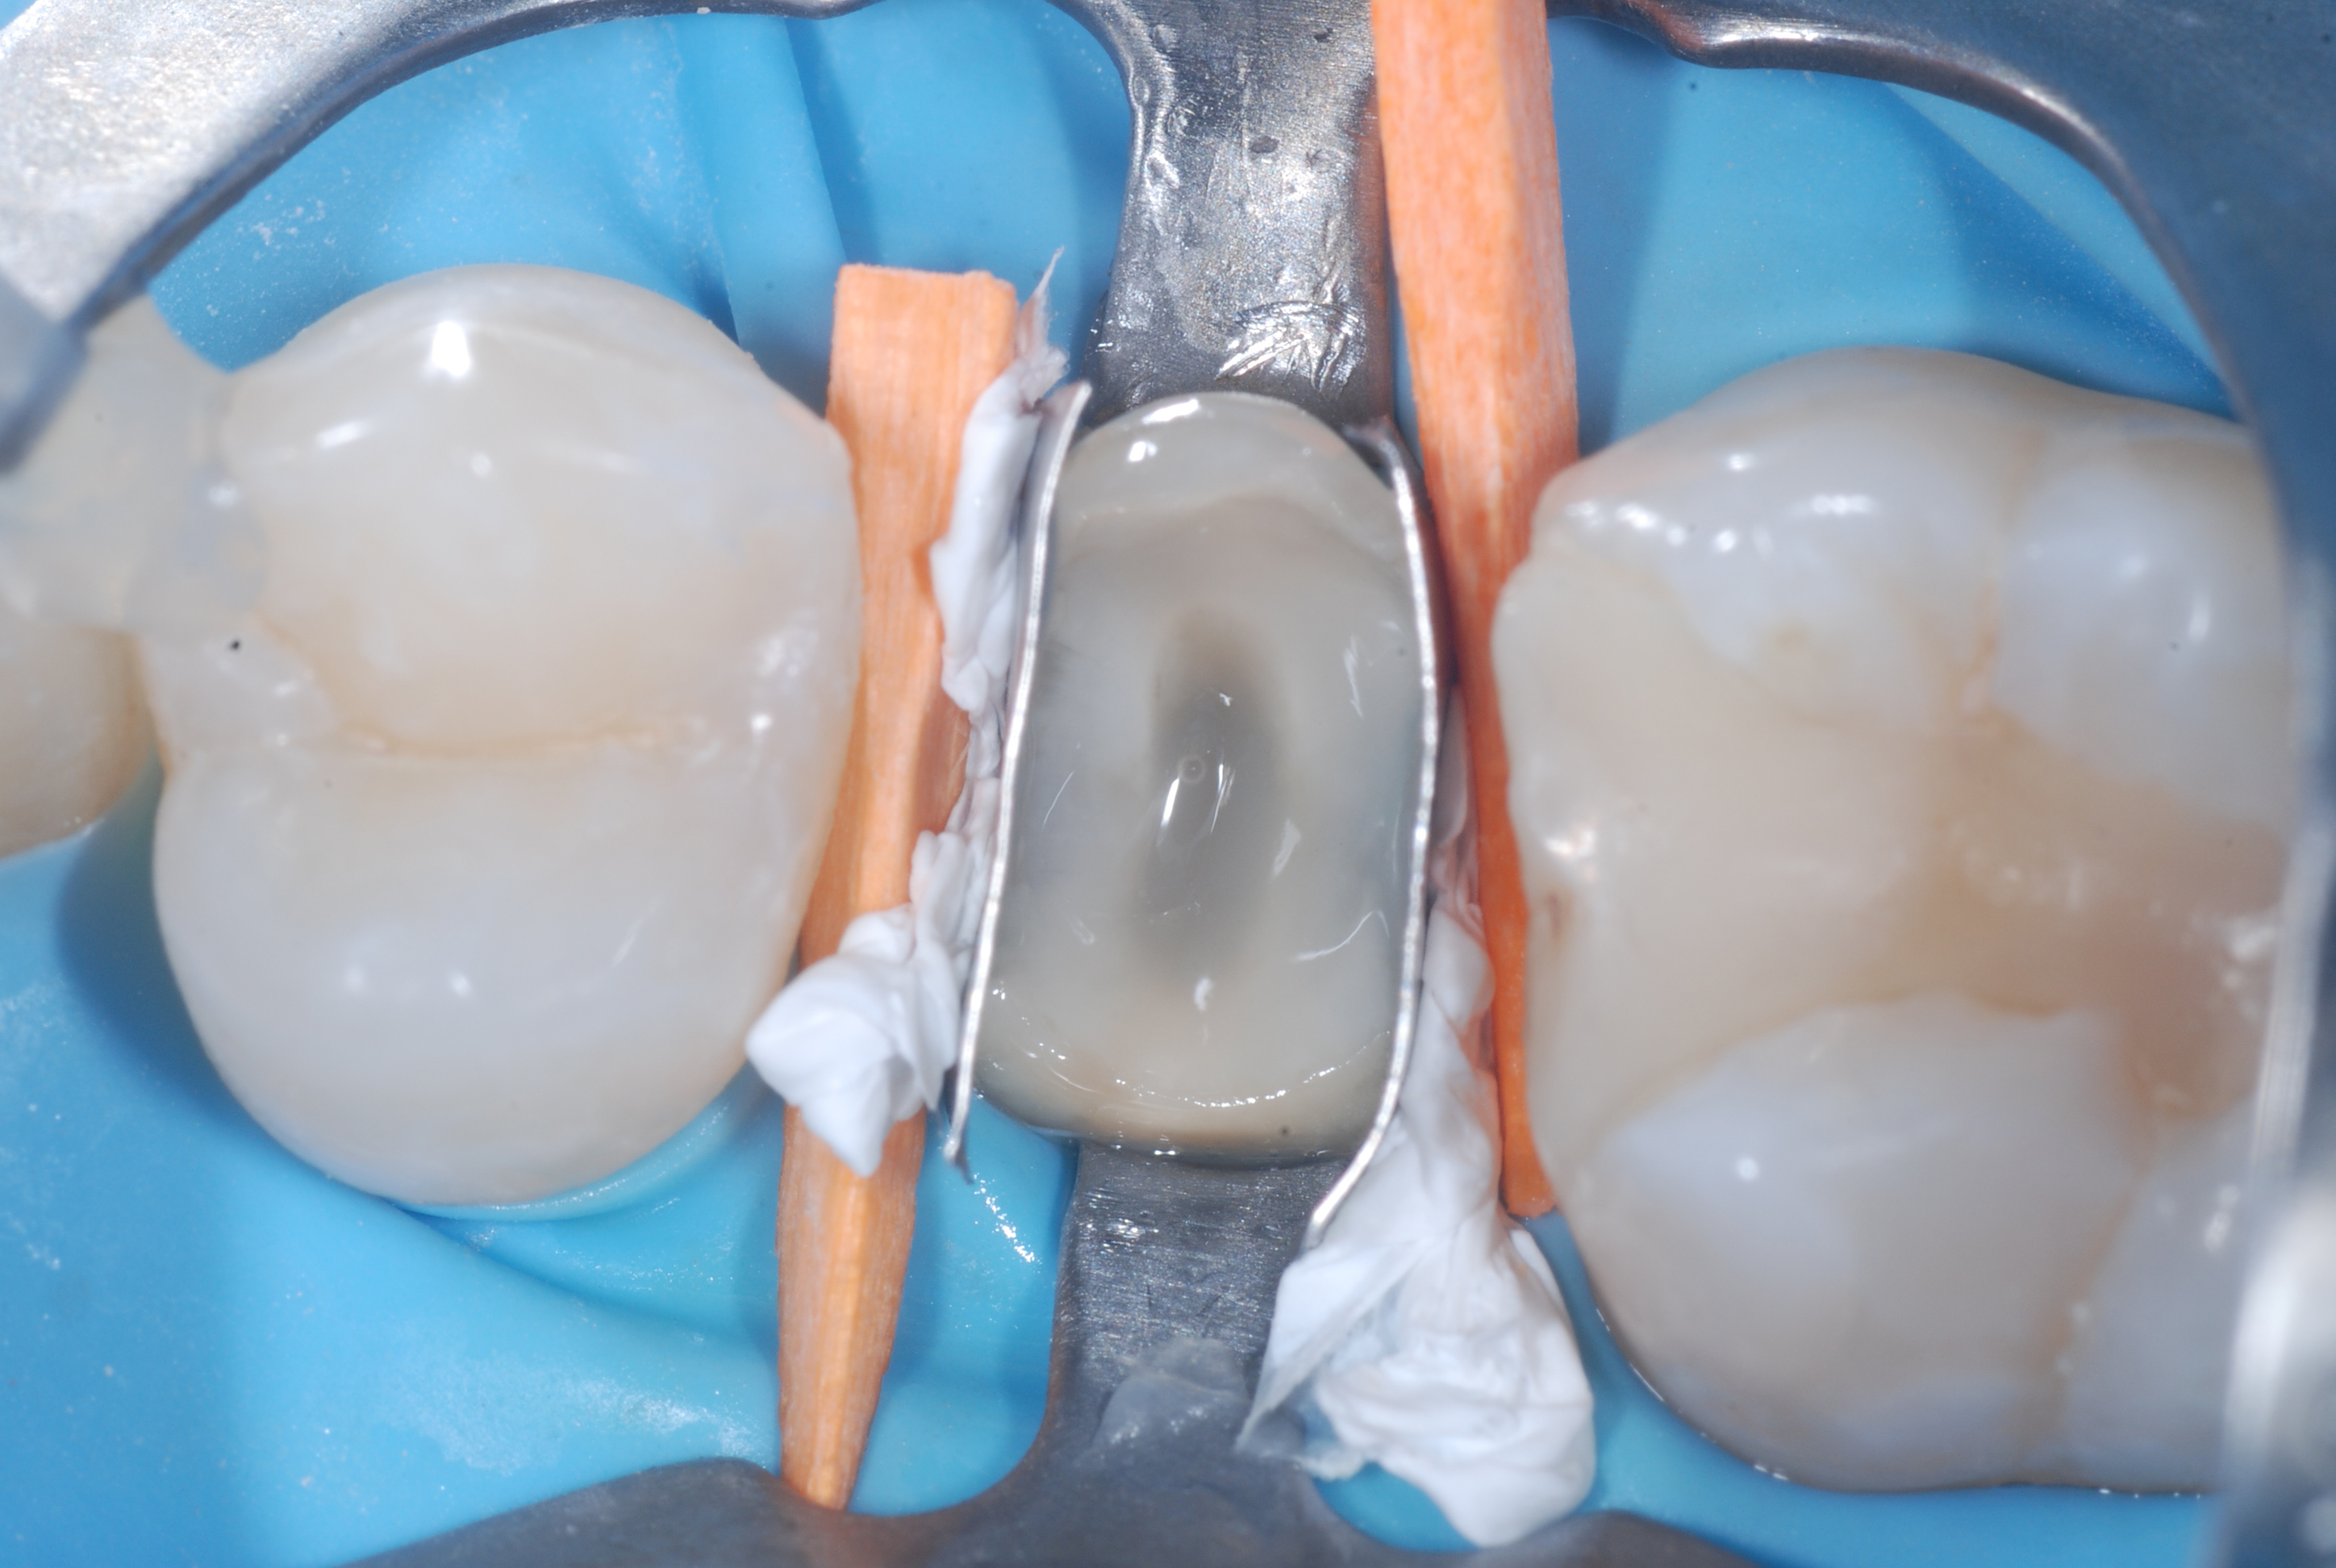

Figure 3. The same tooth immediately after the surgical extrusion.Figure 4. Tooth 25 five weeks after extrusion and endodontic retreatment (carried out by Dr. Francesco Piras). The two points of flowable composite used for splinting after extrusion and the temporary restoration in CVI are still present.

Figure 5. Phase of the adhesive reconstruction of the abutment (Build Up) with flowable composite used as a base. Figure 6. The abutment of tooth 25 just restored with body composite.